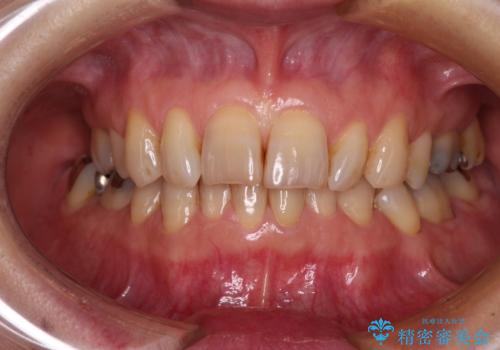

- 下顎前歯が痛んで近医を受診したところ、下顎前歯2本を抜歯してインプラント治療が必要と診断されたとのことで来院された患者様です。

診査の結果、下顎左側中切歯の神経が失活していることが痛みの原因であり、根管治療を行う必要があると診断されました。

根管治療を行った後にオールセラミッククラウンにて補綴することとしました。

隣在歯にも根尖部の炎症が及んでいるように見えましたが、術前診査では神経が失活している様子がなかったため、まずは原因歯から処置を行うこととしました。

初回の根管治療後には痛みが速やかに改善し、6か月後のレントゲン写真では根尖の病変が消失していることが確認できました。